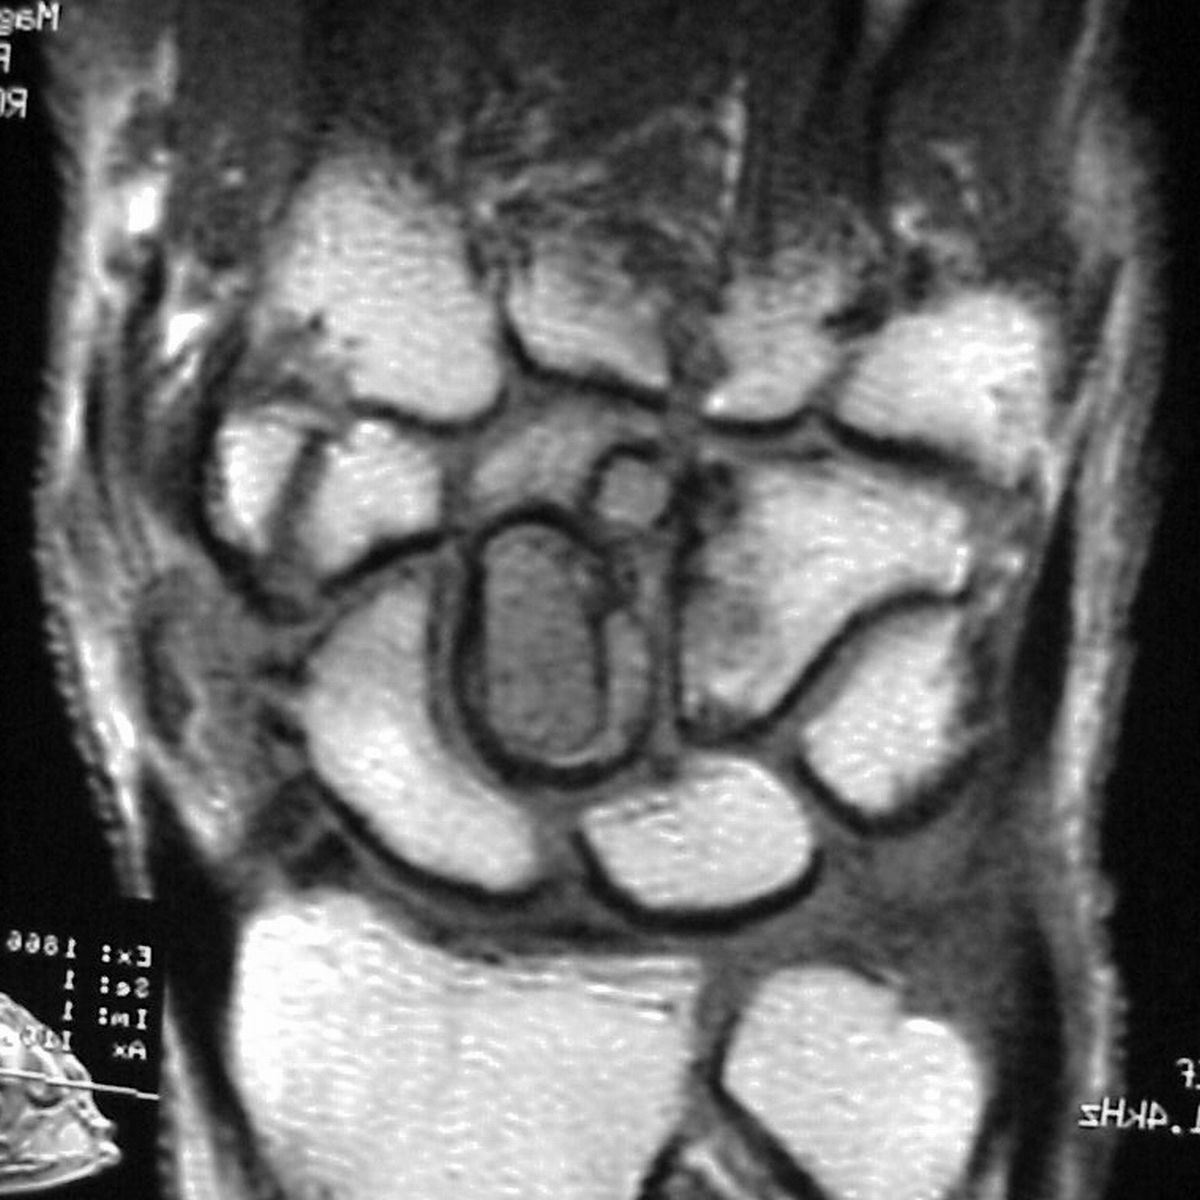

| MRI was

interpreted as inconclusive, differential including an

intraosseous cyst or giant cell tumor with cortical

thinning but no suggestion of malignancy. |